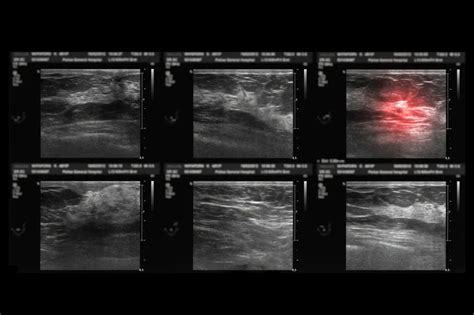

乳房出现硬块可能是哪些情况?资讯攻略12-03

乳房出现硬块可能是哪些情况?资讯攻略12-03 -